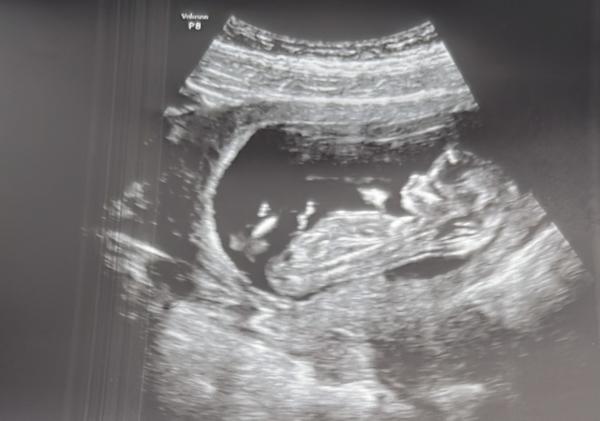

Natürlich Hauptsache gesund. Aber nachdem das 1. Trimester Screening vorüber ist und wir ein gesundes Baby haben ist man ja nun doch neugierig ob es ein Junge oder ein Mädchen wird. Kann jemand was erkennen :)?

Bild zu Mädchen oder Junge? Erkennt jemand was? - Schwanger - wer noch? Rund um die Schwangerschaft

Guten Abend Memyselfandi,  verstehe dich voll. Und natürlich sind wie Laien, aber man kann ja nunmal raten und die Wartezeit ein bisschen damit vertreiben 😊  Ich würde tatsächlich auf einen Jungen Tippen. Beim ersten Bild liegt euer Mäuschen recht gerade und der Nub deutet ein wenig nach oben.  Bin auf jedenfall gespannt, wie das Ergebnis sein wird...  Natürlich noch Herzlichen Glückwunsch zur Schwangerschaft und schön, dass sich euer Baby so toll entwickelt 😊

Lieben Dank für deine Nachricht und dein Tipp. Ich war mir unsicher ob dass der Nub ist oder die Nabelschnur. Es ist einfach so spannend :)

oh wie toll :) Erkennt man anhand des Nubs auf den ersten Bild ?